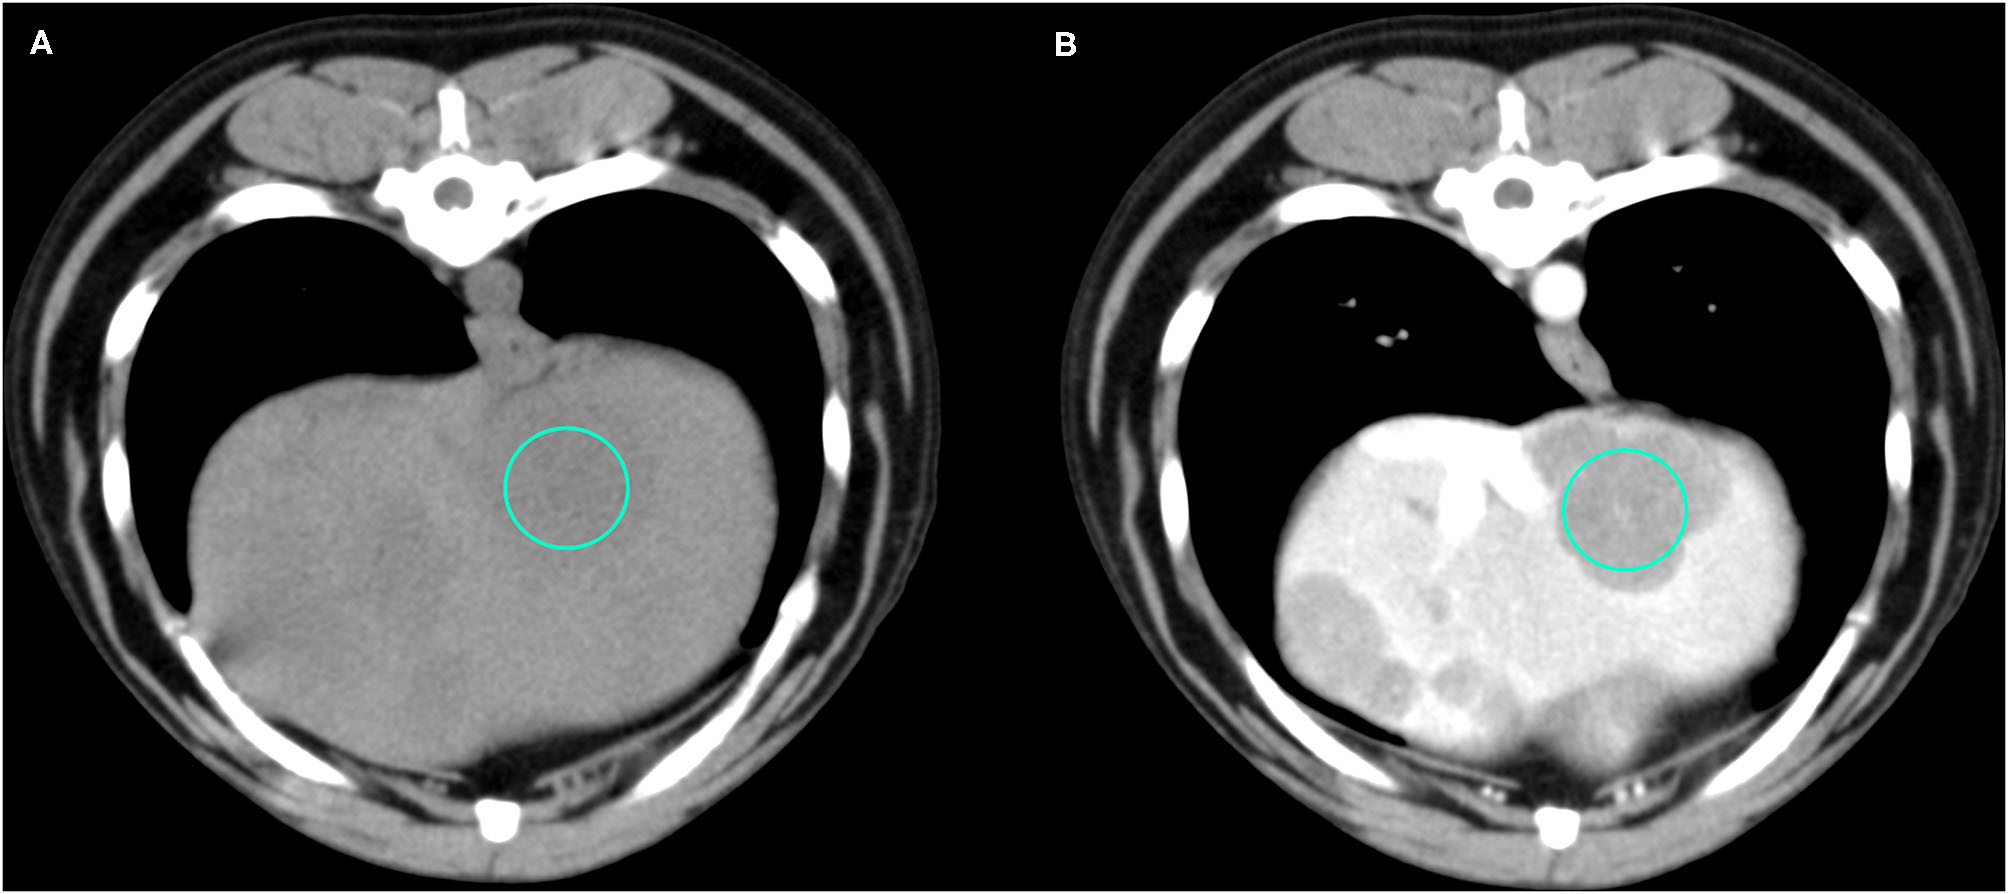

Figure 4

Example of an OML (diagnosed as lymphoma) showing hypoattenuation and hypoenhancement, diffuse contrast enhancement pattern, with heterogeneous distribution, well-defined margins, irregular surface, and solid appearance. (A) image obtained from the pre-contrast scan; (B) image obtained from the delayed scan. A ROI is placed inside the lesion in both. Based on the developed decision tree this lesion was classified as OML.